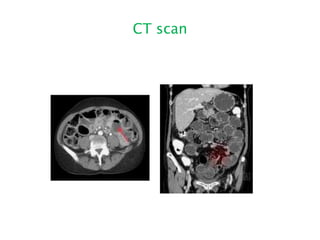

CT scan

Radiology Small Bowel Obstruction Central distention (GAS)  Valvulae conniventes  “Ladder-like dilatation”  Small diameter Large Bowel Obstruction  Peripheral distention “Picture frame”  More gross distention  Haustral indentation & large diameter